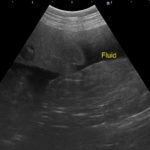

歯茎白い。すぐさま腹部の超音波検査をして”腹腔内液体貯留と腹腔内腫瘤を確認”

エコーでは脾臓と肝臓にMASSを確認。